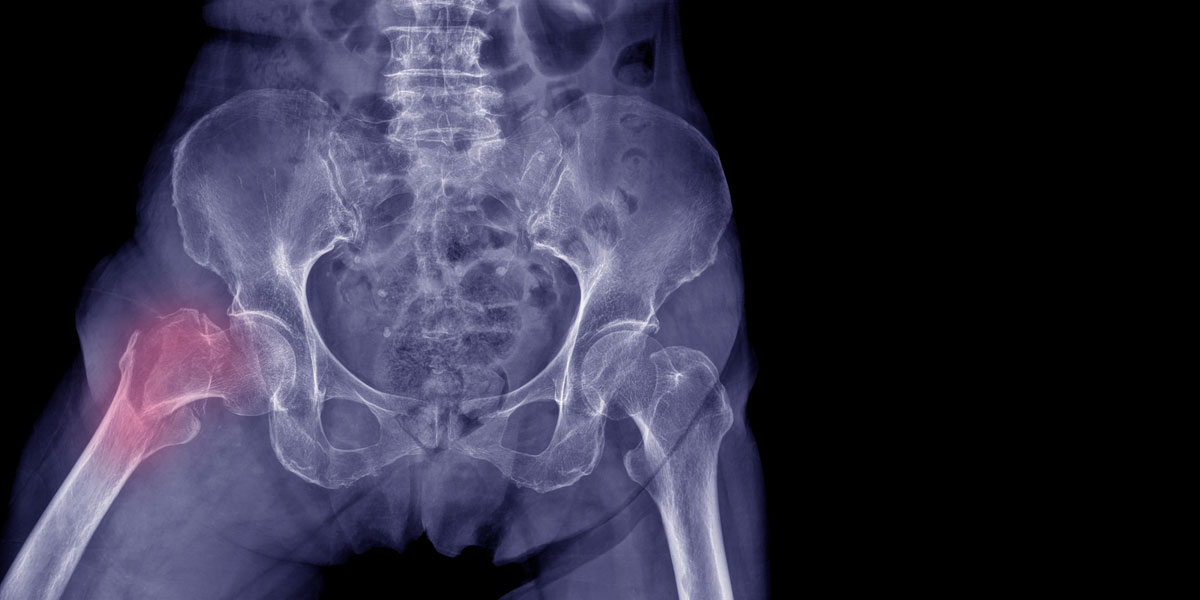

Τι είναι το Κάταγμα Ισχίου; Το ισχίο είναι το σημείο του σώματος, όπου η μηριαία κεφαλή του μηρού ενώνεται με την λεκάνη και μέσω αυτού …